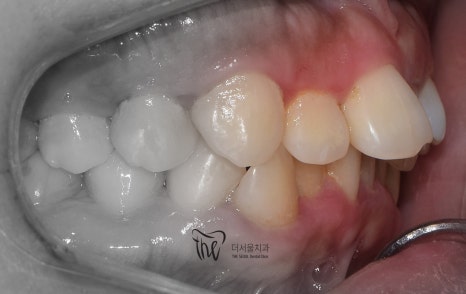

이 분은, 부정교합 2급 인데도 돌출입의 정도가

그리 심하지는 않습니다.

심미선을 기준으로, 입술이 살짝 걸리는데

이 정도라면 비발치로도 진행이 가능한 부분입니다.

다만, 앞니들이 앞쪽으로 많이 뻐드러져

있기 때문에 입술의 긴장감이 많이 형성이

되어있는지라 이 부분은, 치아 재 배열을

통해서 충분히 개선이 가능할것으로 보여집니다.

측면에서 봤을 땐, 앞니들의 뻐드러짐과

불규칙한 치열을 동시에 관찰을 할 수 있습니다.